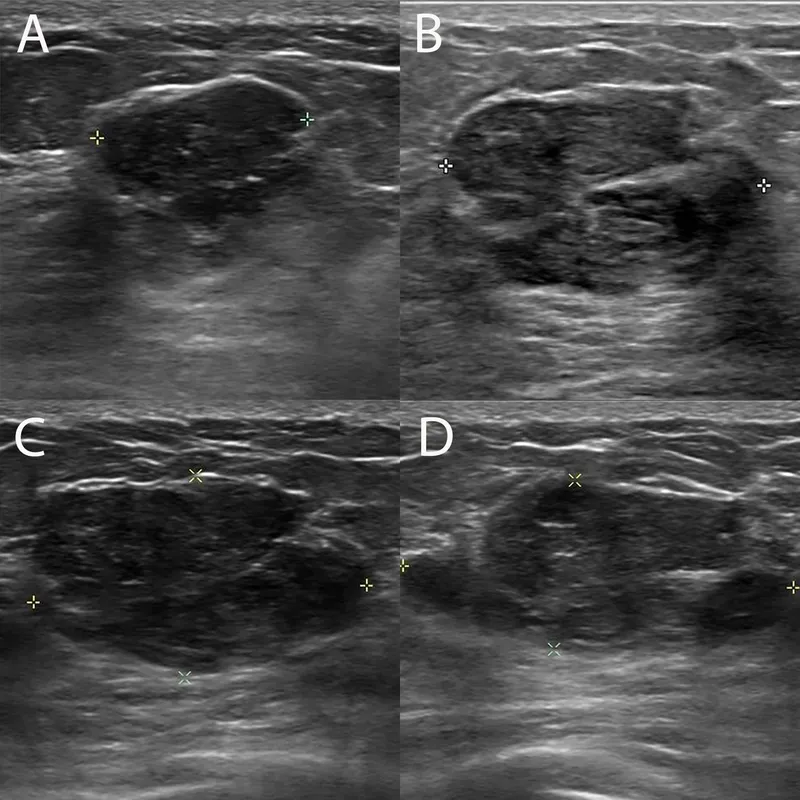

- USG: Hypoechoic, wider-than-tall.

- USG: May show cystic spaces.